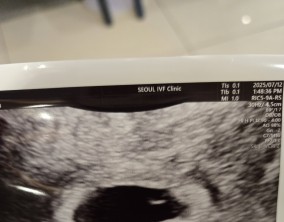

설렘과 불안의 시간을 지나 찾아온 선물

서울IVF여성의원의 난임 치료는 과정 하나하나가 체계적이고 세심하다는 인상을 받았습니다. 이유정 원장님과 간호사 분들께 치료 단계마다 충분한 설명을 들을 수 있어 불안이 많…